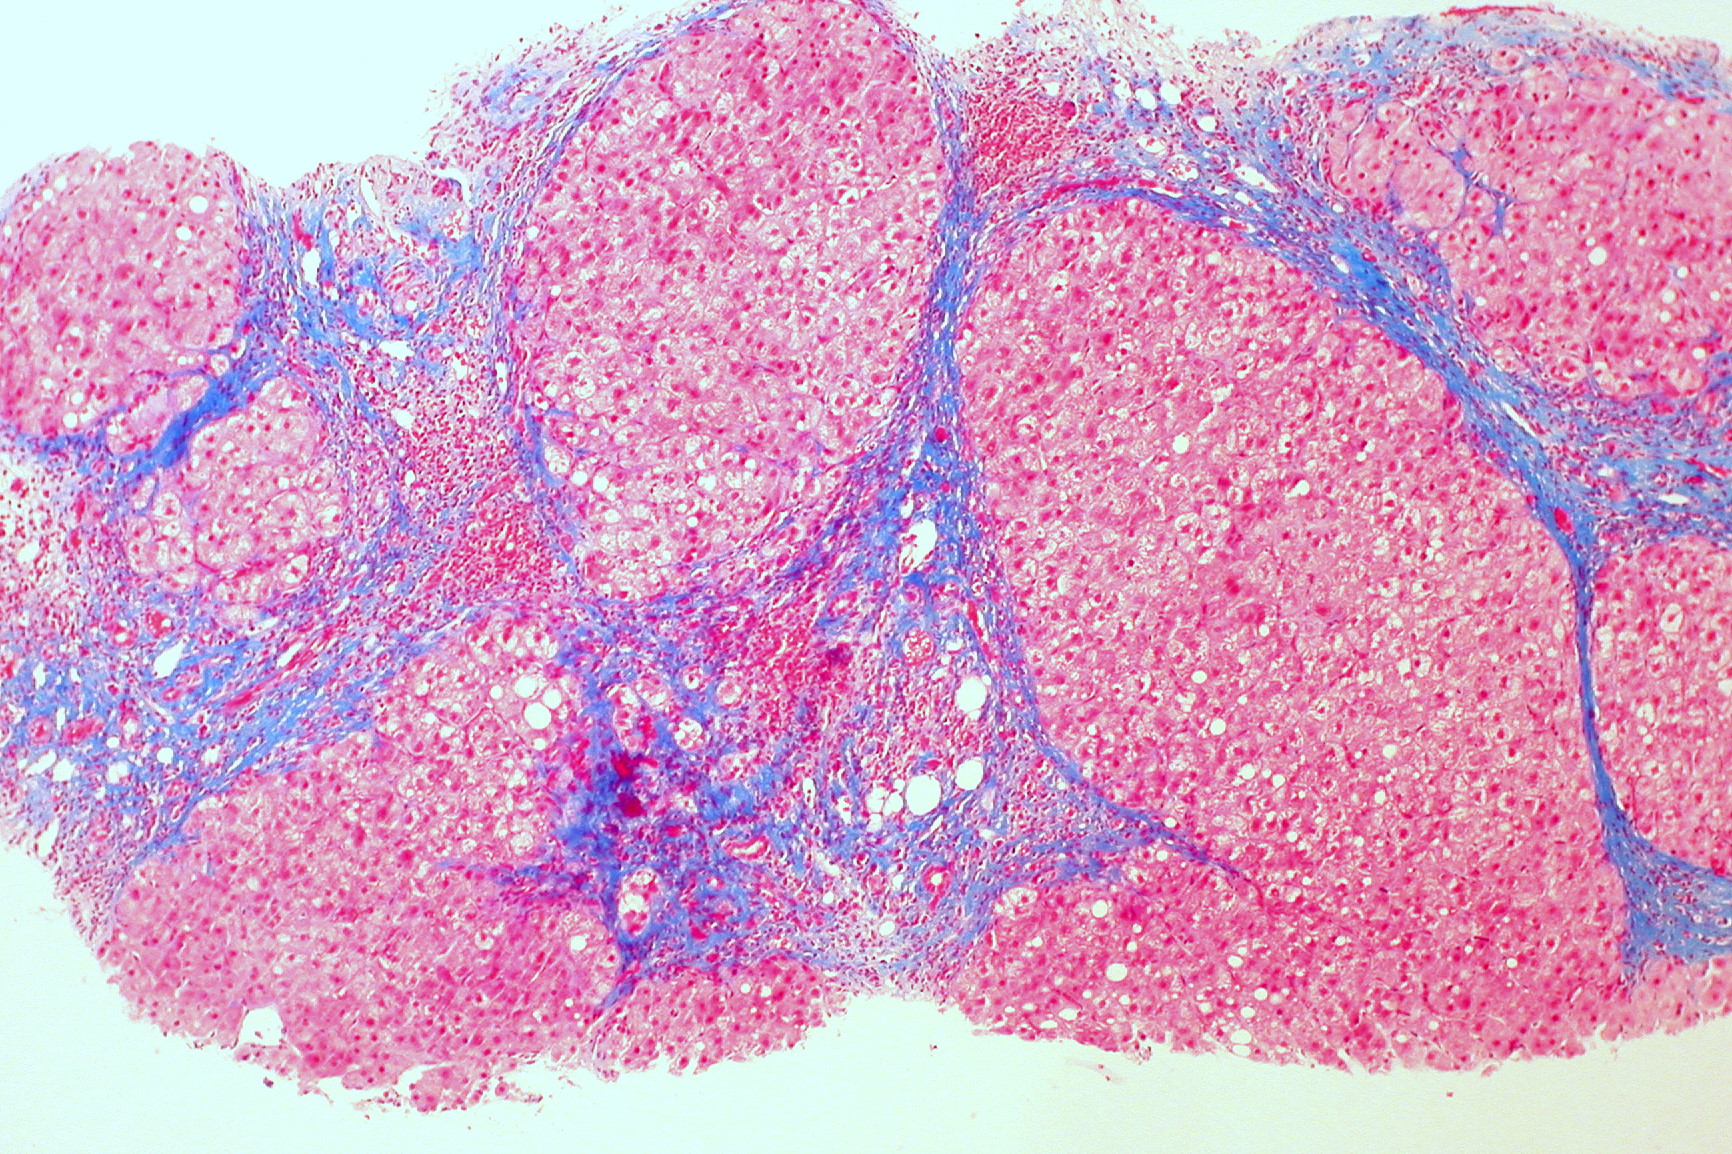

La cirrhose est une maladie du foie, le plus souvent causée par une consommation chronique d’alcool, mais parfois en raison d’une infection à l’hépatite B ou C (cirrhose hépatique). D’une manière générale, elle est considérée comme le plus grand facteur de cancer du foie, mais les traitements peuvent freiner la progression de la maladie, voire la faire régresser (transplantation hépatique).